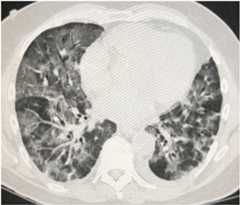

Over the first days of hospitalization, the patient’s oxygen requirement gradually worsened; his white blood cell (WBC) count and C-reactive protein (CRP) continued to increase. Point-of-care ultrasound revealed worsening B lines (Figure 1). Despite the addition of lopinavir and ritonavir and switching antibiotics to meropenem and vancomycin, he developed and maintained a low-grade fever. Computed tomography of the chest revealed diffuse ground-glass opacities consistent with acute respiratory distress syndrome (ARDS) (Figure 2). On the fifth day after diagnosis, the patient’s oxygen requirement and work of breathing dramatically worsened, and he was intubated and placed on a ventilator for respiratory support.

Figure 2.

Computed tomography revealing bilateral infiltrates consistent with acute respiratory distress syndrome.